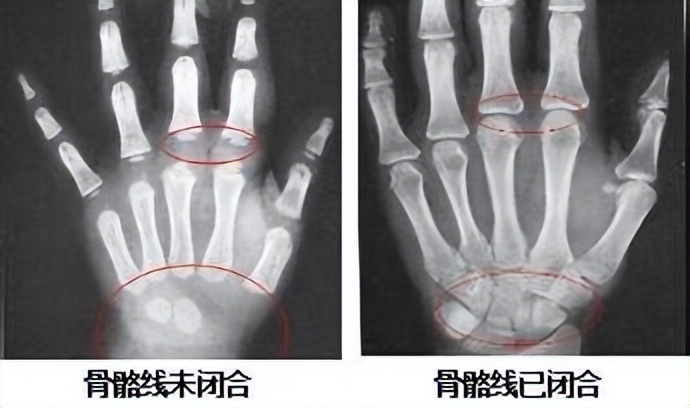

骨龄就是骨骼年龄。是骨骼发育进程的年龄描述,代表了特定正常人群中各个不同年龄未成年人骨骼发育的一般状态。

意义: 以骨骼发育变化测定体格发育年龄( 同年龄儿童,发育程度可不一致 )。通过测定骨骼的大小、形态、结构、相互关系的变化来反映体格发育程度即以骨骼的发育变化测定发育年龄,通过统计处理,以 岁 为单位表达生物学年龄

骨龄是体格发育的 基本指标,与成年终身高直接相关。